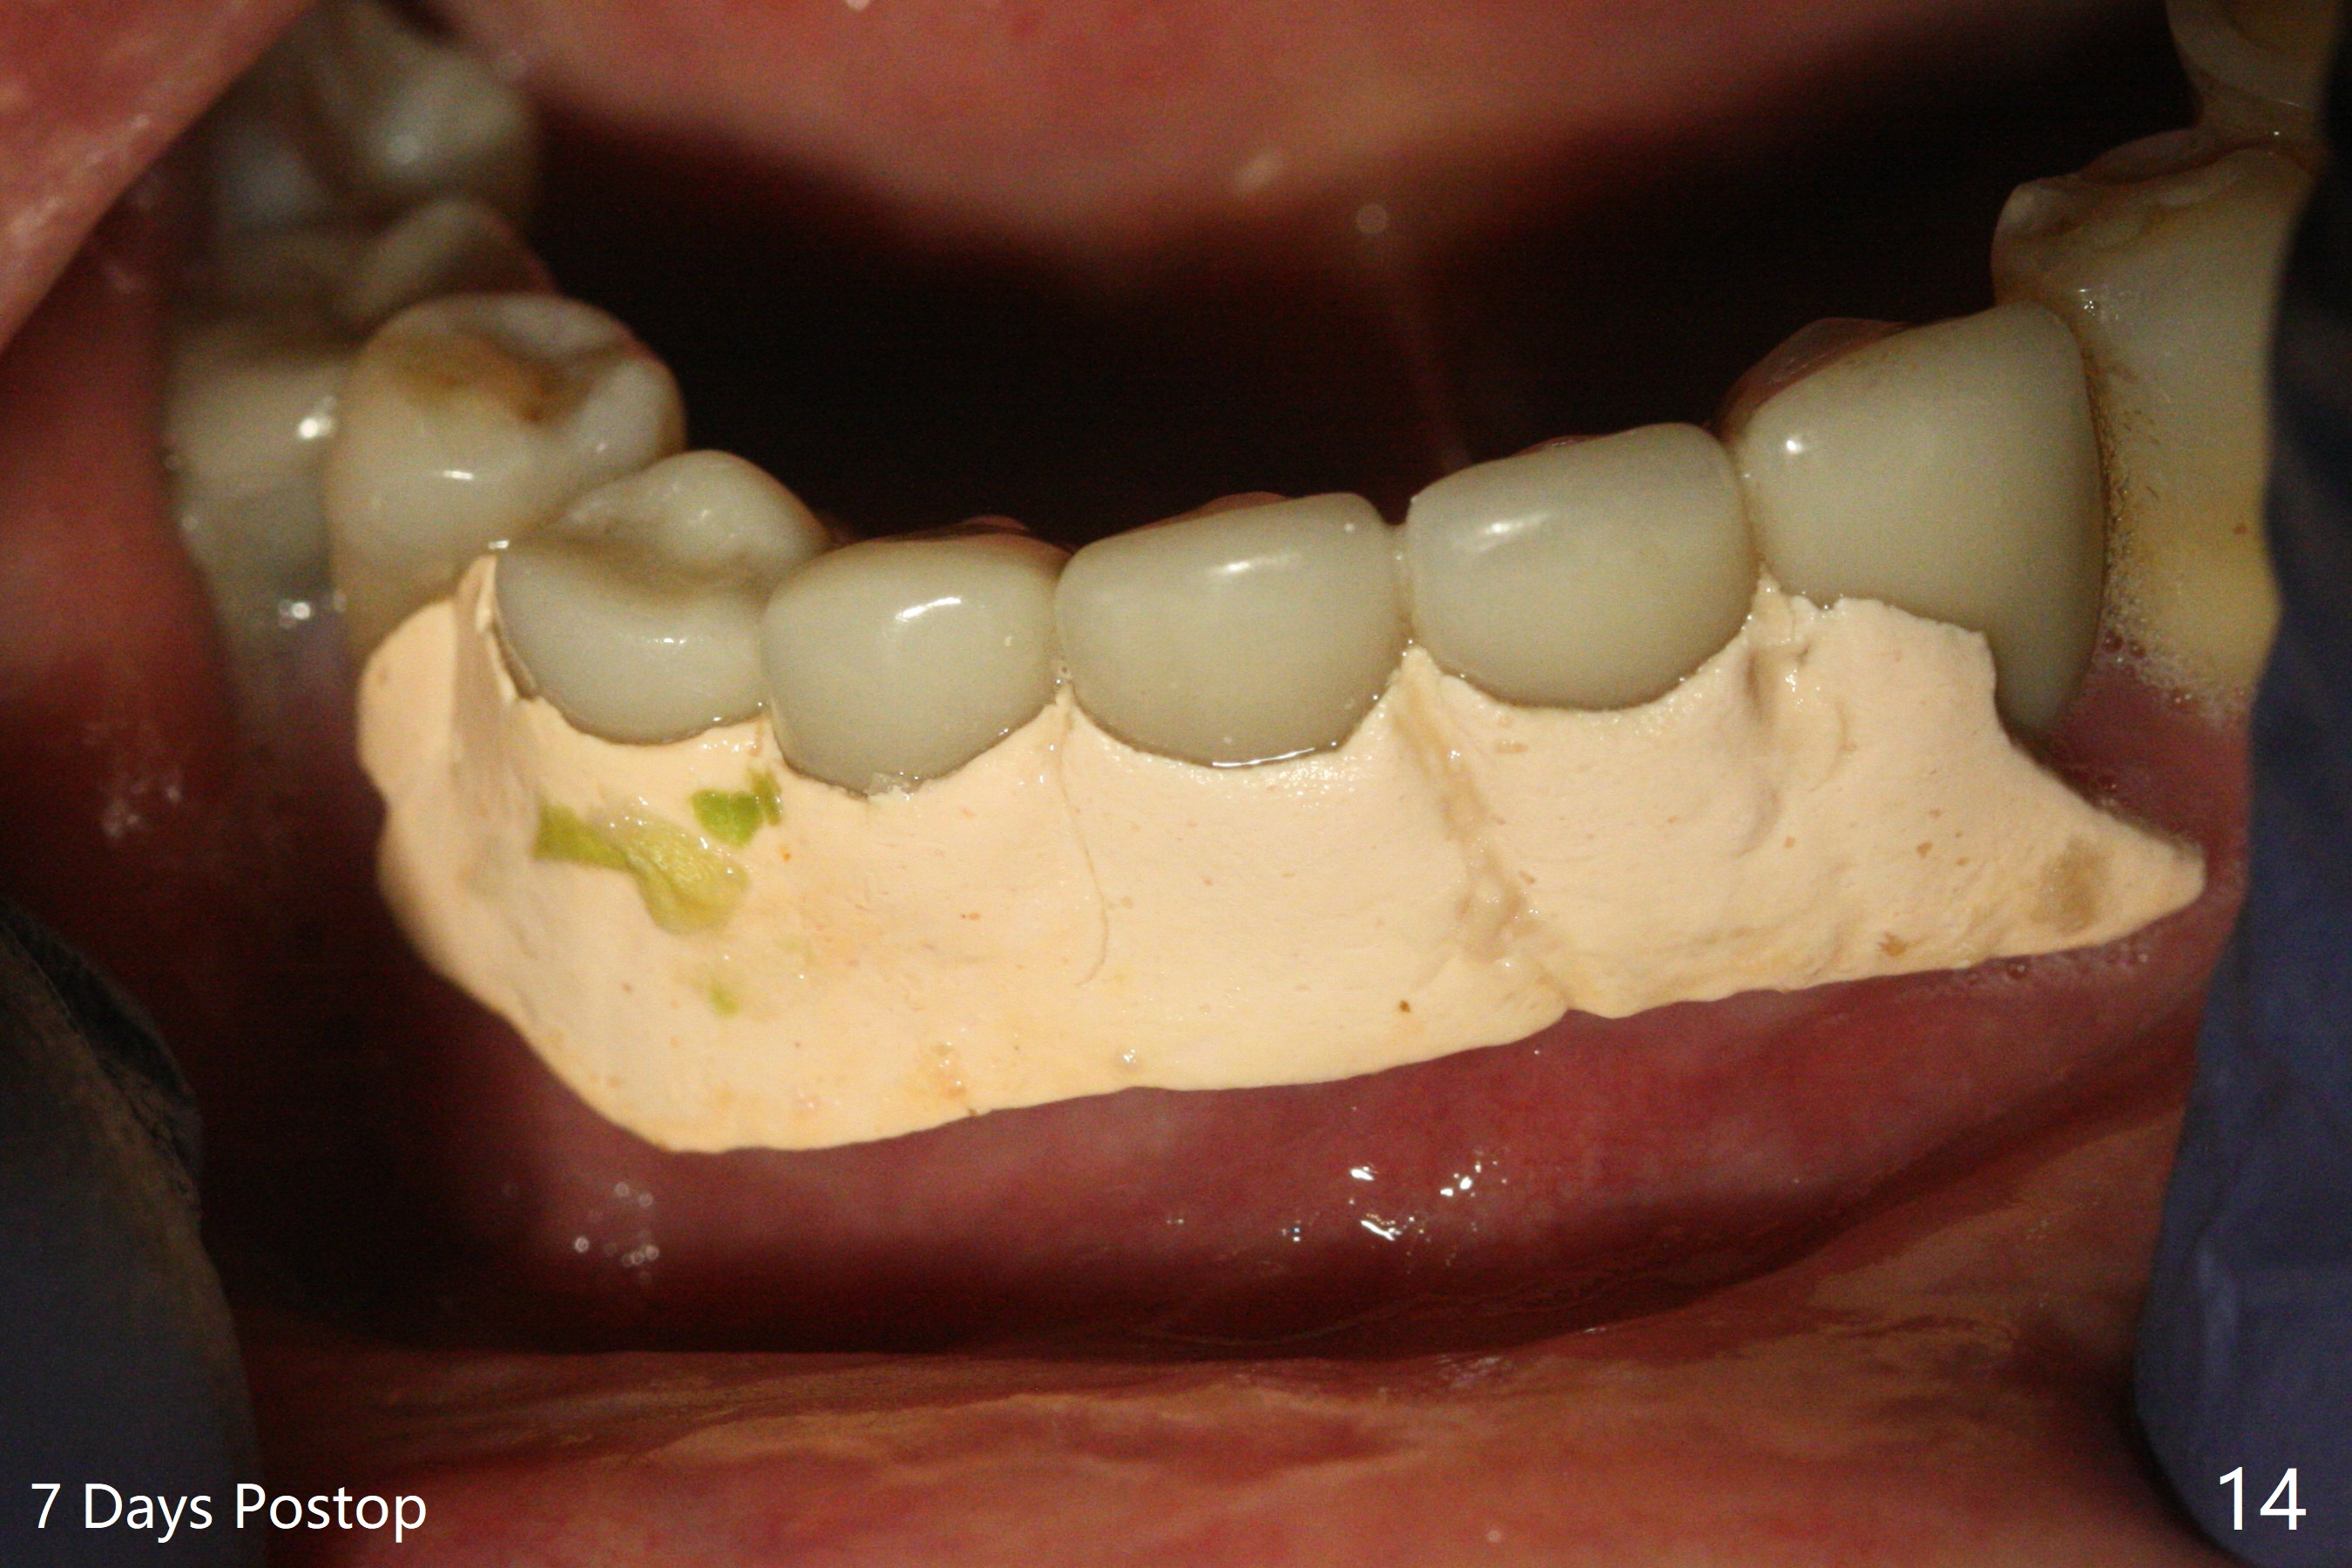

The implants remain asymptomatic years months post cementation (Fig.12), while the one at #27 is associated with buccal and lingual swelling and hemorrhage and bone loss (Fig.13).  There is bone loss distal to #27 without symptom 3 years 9 months post cementation (Fig.12).  Periimplantitis develops buccal and lingual 4 years 5 months post cementation (coronavirus, Fig.13).  Sticky bone and PRF are used after debridement.  There is no discomfort 7 days postop (Fig.14,15).